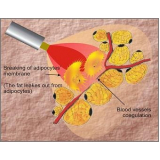

Lipoaspiração a Laser

Você merece a qualidade e comprometimento entregues pela equipe deste consultório médico e se neste momento está à procura de uma equipe que realize lipoaspiração a laser saiba que a FF Cirurgia Plástica disponibiliza de imediato este serviço para você!

Lipoaspiração a laser: atendimento eficiente e com qualidade que você sempre buscou!

Neste consultório médico você encontrará profissionais eficientes e com experiência de excelência. Usufrua de bom atendimento, através dos melhores preços do mercado e de assistência especializada sempre à sua disposição! Leve as suas dúvidas, converse com a equipe da FF Cirurgia Plástica. Contrate bons serviços e sinta-se mais seguro para cuidar da saúde.